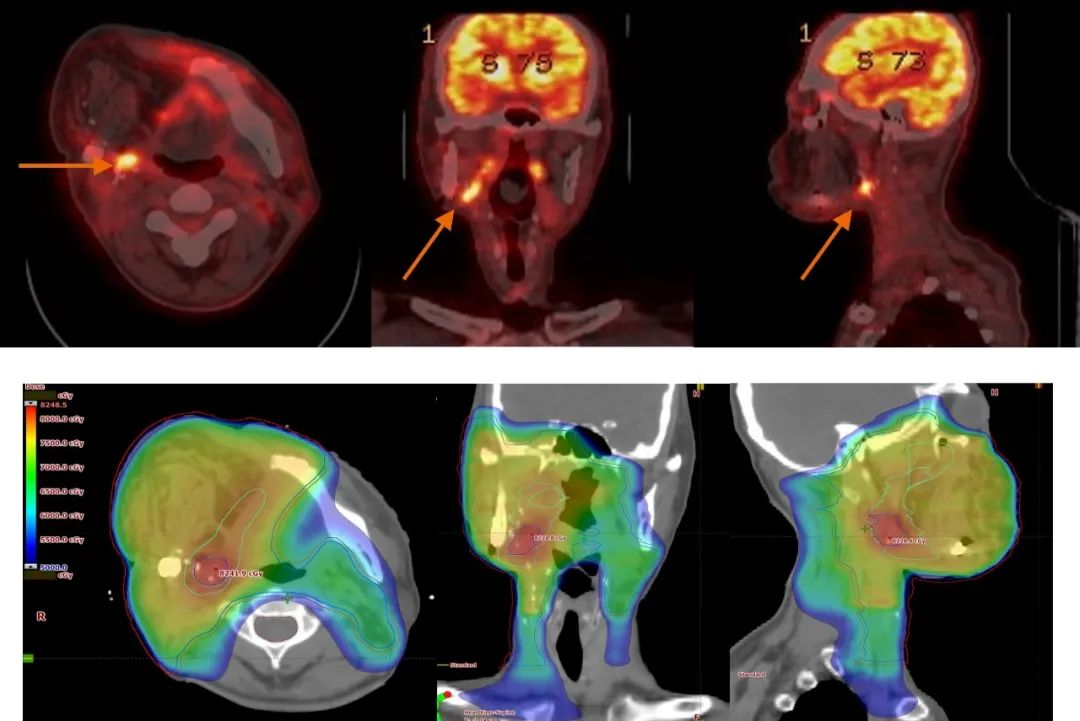

上面病例為一名70歲女性患者,口腔癌手術切除后,Biograph mCT PET/CT檢查后發現局部攝取增加,提示復發,CT未見該腫塊。而后基于PET/ CT制定放療計劃,放射治療后3個月和15個月的PET/CT隨訪顯示無復發。功能學影像有助于確定術后腫瘤床內的功能性腫瘤體積,以增加劑量。